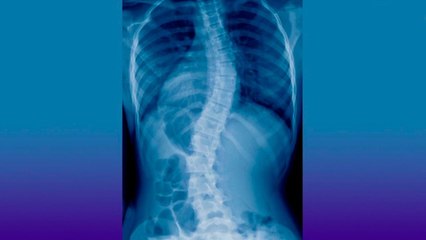

Gracias a la asociación "EscoAyuda", decenas de pacientes que padecen escoliosis pudieron ser operados gratuitamente para tratar las desviaciones en su columna vertebral.